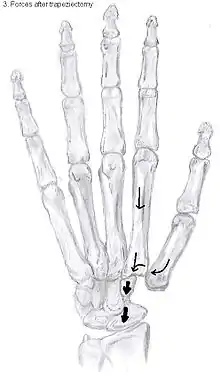

Types of trapeziectomy

The principle of this procedure is the removal of the trapezium bone. It was originally described by Gervis in 1949 [24]. Because half of the carpometacarpal joint is removed, the complaints of patients caused by OA are usually gone.

Four main varieties within this procedure are performed:[32]

- Trapeziectomy

- Trapeziectomy with tendon interposition (TI)

- Trapeziectomy with ligament reconstruction (LR)

- Trapeziectomy with a combination of ligament reconstruction and tendon interposition (LRTI)

Trapeziectomy

The most simple form out of the four variations is the trapeziectomy alone, also referred as the simple trapeziectomy.[32] During this procedure, the trapezium bone is removed without any further surgical adjustments.

The trapezium bone will be removed through an approximately three centimeter long incision along the lateral side of the thumb. To preserve surrounding structures, the trapezium bone will be removed through fragmentation of the bone (the bone will therefore be broken into pieces).

An empty gap is left by the trapeziectomy and the wound is closed with sutures. Despite this gap, no significant changes in function of the thumb are reported.[31] After the surgery, the thumb will be immobilized with a cast.